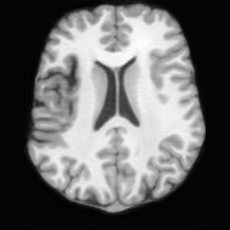

(a)PathologicalInput ImageSynthSR [18]Brain-ID [28]UNA [30]USBHealthyGround TruthRefer to captionRefer to captionRefer to captionRefer to captionRefer to captionRefer to captionRefer to captionRefer to captionRefer to captionRefer to captionRefer to captionRefer to captionRefer to captionRefer to captionRefer to captionRefer to captionRefer to captionRefer to captionRefer to captionRefer to captionRefer to captionRefer to captionRefer to captionRefer to caption(b)HealthyInput ImageConditionalLesion MaskUNA [30]USBRefer to captionRefer to captionRefer to captionRefer to captionRefer to captionRefer to captionRefer to captionRefer to captionRefer to captionRefer to captionRefer to captionRefer to captionRefer to captionRefer to captionRefer to captionRefer to caption

Figure 5: Comparison of bidirectional brain editing. (a) pathology-to-healthy, the circles and arrows highlight lesion regions and unsuccessful reconstructions; (b) healthy-to-pathology. Note that SynthSR and Brain-ID cannot perform healthy-to-pathology editing.

Healthy-to-Pathology Editing. As shown in Fig. 5 (b), given a healthy brain image paired with a random lesion mask, USB seamlessly embeds the lesion into the healthy anatomy, producing realistic pathological appearances consistent with surrounding structural context. Yet UNA’s syntheses are visually unrealistic, with the conditioned lesion mask simply overlaid as a parallel layer onto the healthy brain. Tab. 3 further demonstrates USB’s superior performance. The evaluation was conducted on 100 pairs of lesion masks and healthy brains, with real stroke images

from ATLAS dataset used as reference for FID, KID, and MMD. USB consistently outperforms UNA across all metrics.